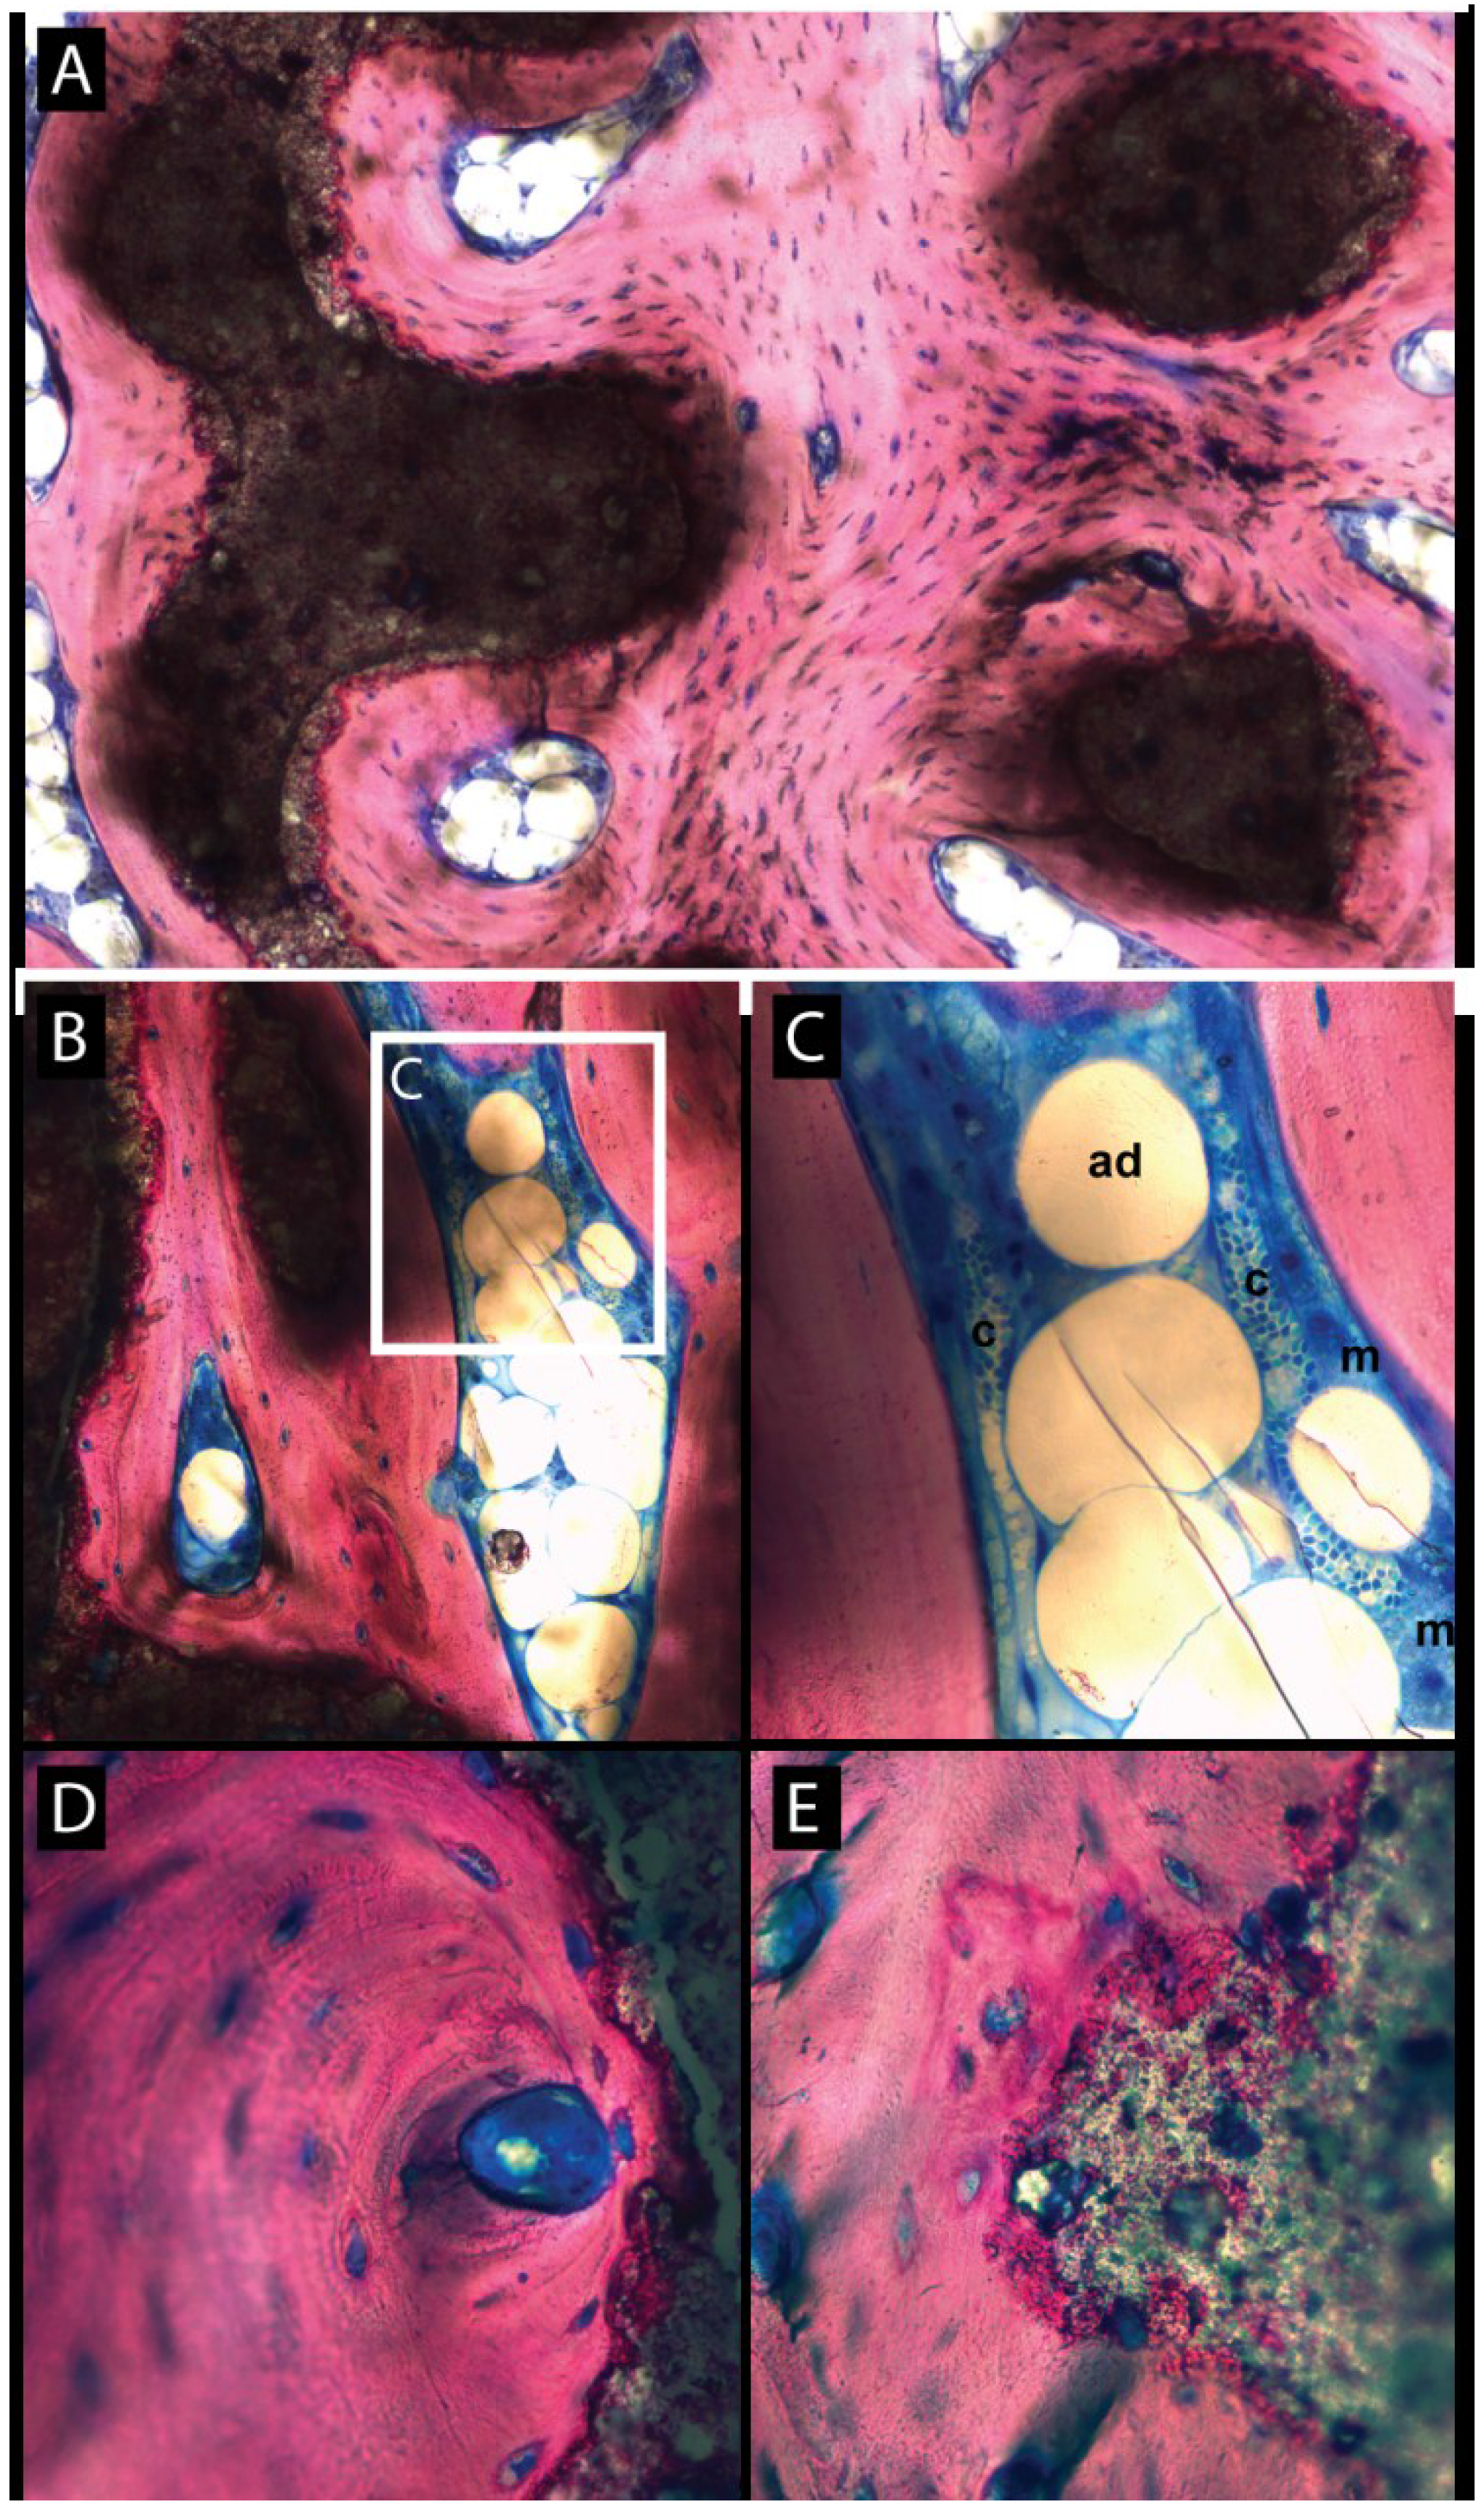

3.2. Histologic Evaluation